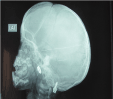

The father presented to the clinic before with the same clinical (Figure 8) and radiographic signs of CCD. Anterio-posterior view for the skull revealed persistent sagital sutures with multiple wormian bone (Figure 9). Chest X-ray showed absent of the distal third of both clavicles (Figure 10) He was presented before with many impacted and supernumerary teeth and with multiple carious and badly destructed teeth. He was treated by extraction of the badly destructed teeth (Figure 11) and construction upper and lower removable partial denture (Figure 12). The father was happy and satisfied with this kind of treatment.

Figure 9. Anterioposterior skull view